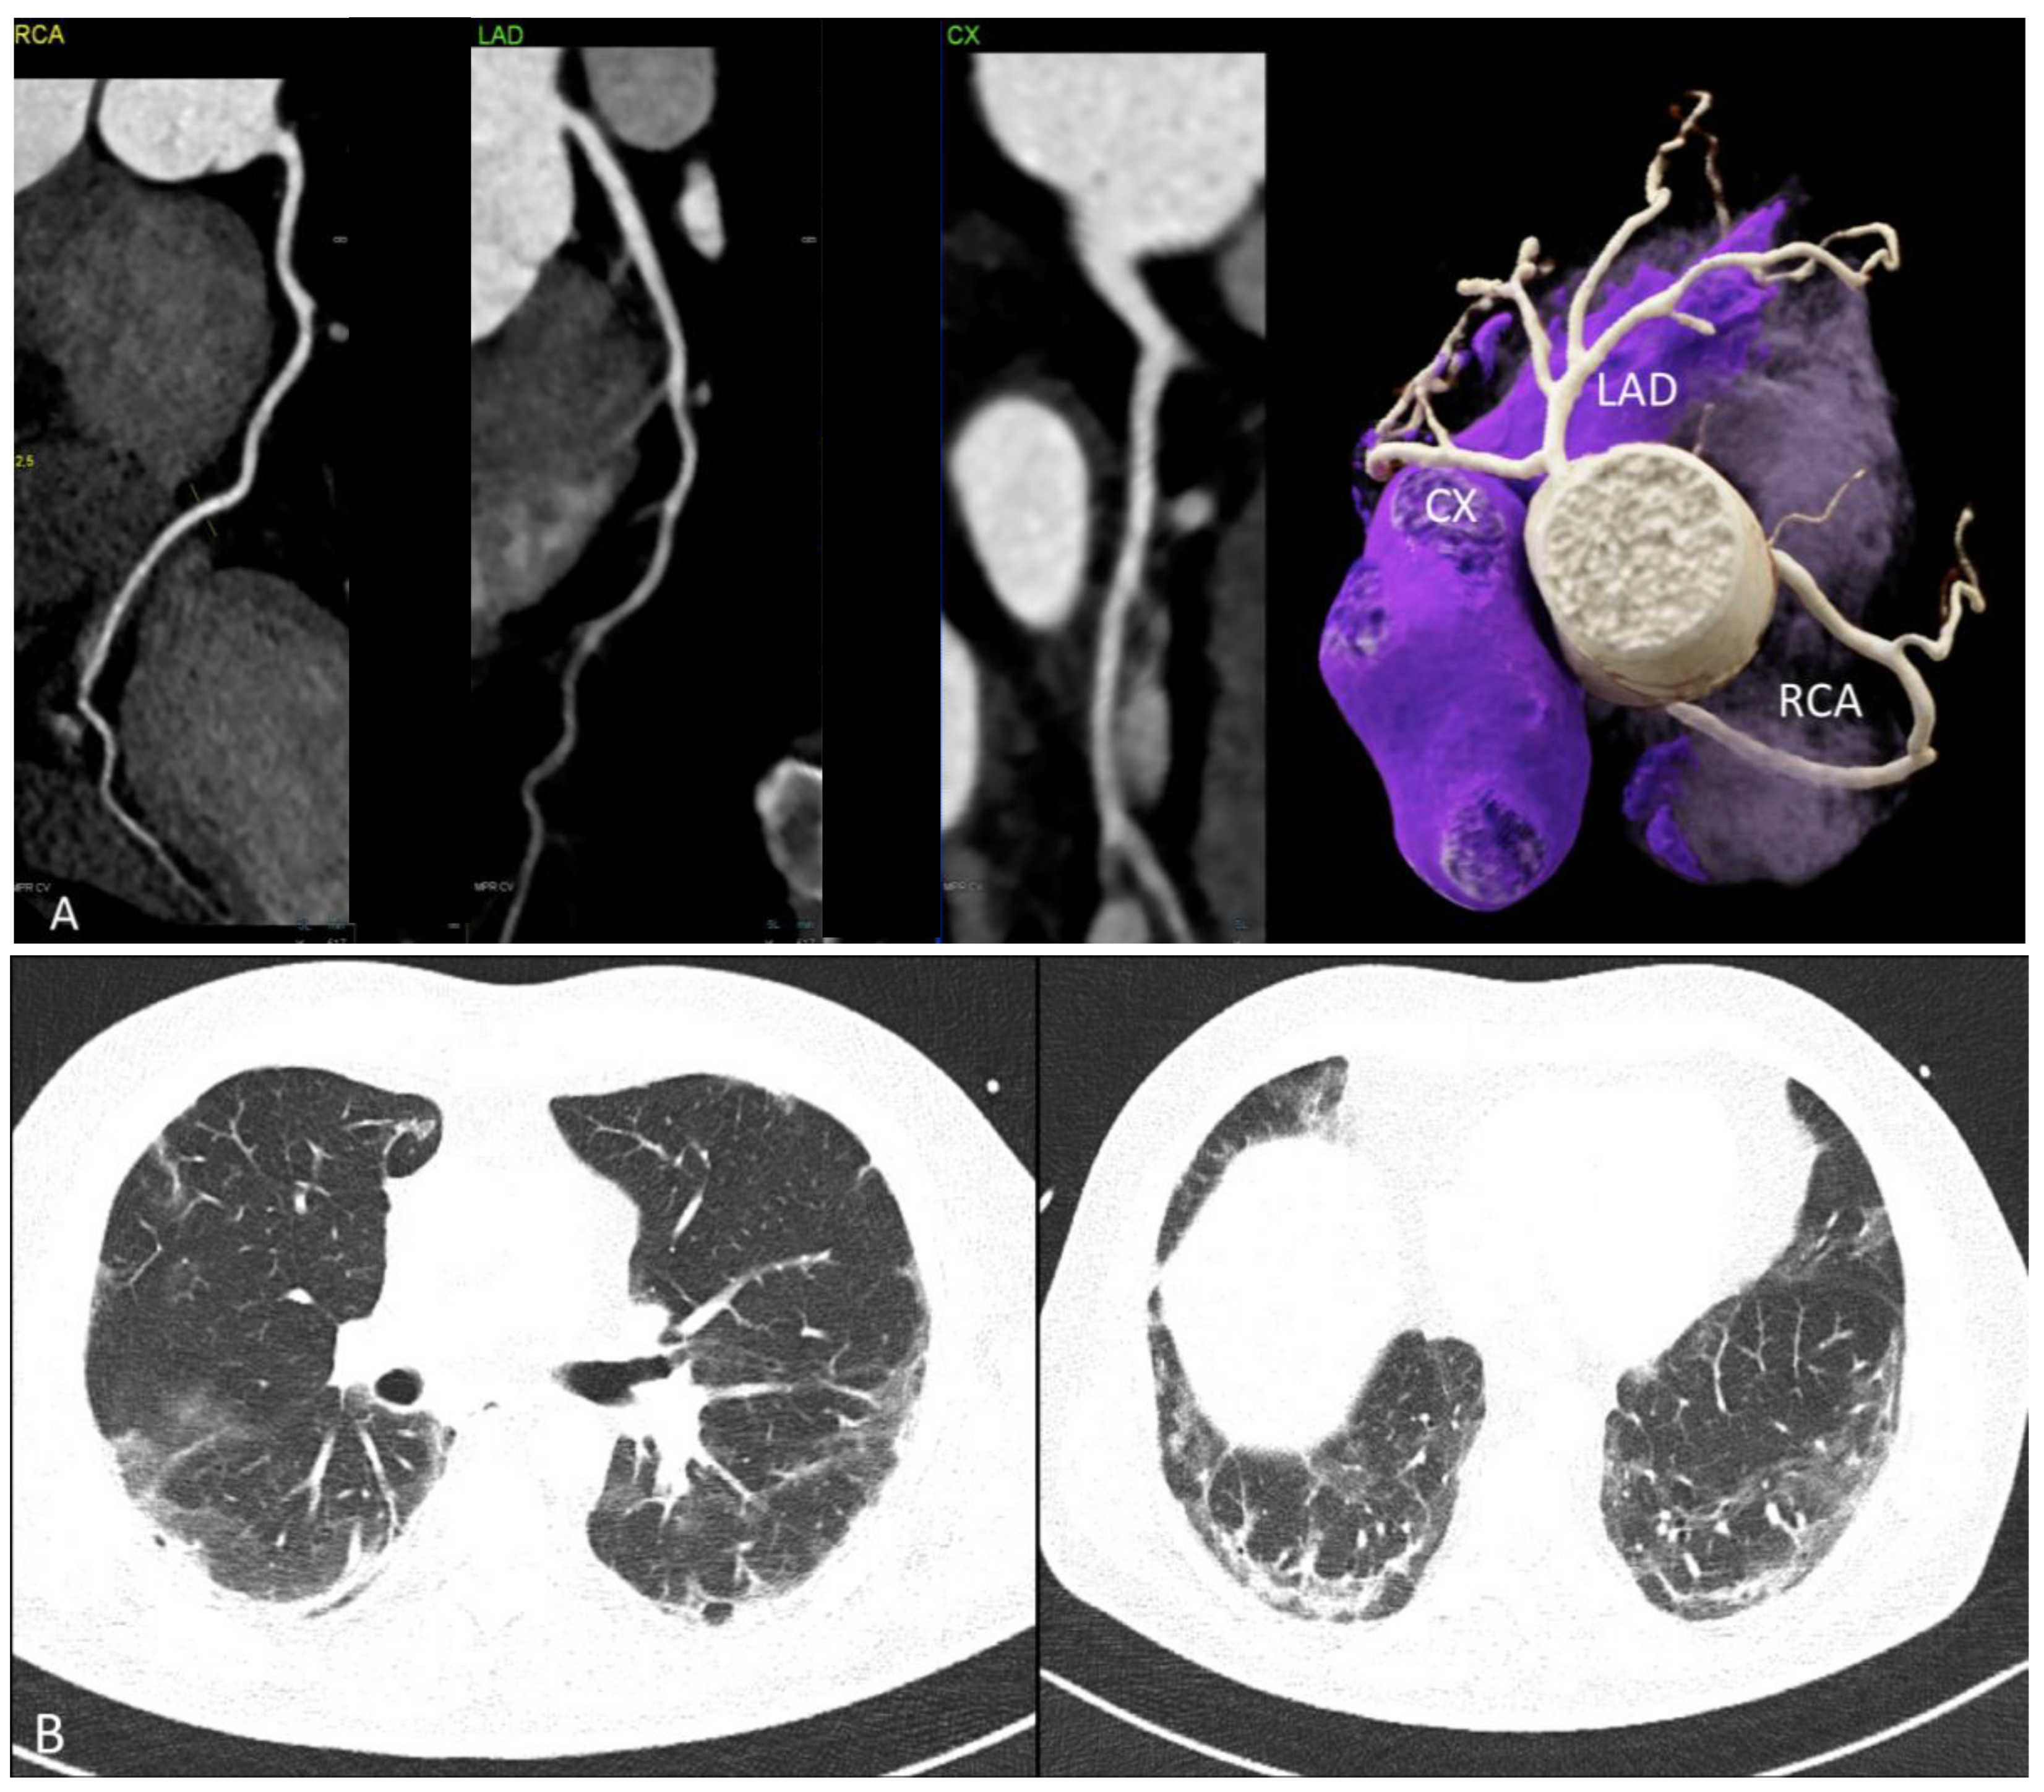

| CTA findings | ||

| Acute, unstable N = 4 | Stable N = 8 | |

| Coronary artery disease by CTA | 1 (25%) | 4 (50%) |

| Nonobstructive (<50% stenosis) | 0 (0%) | 2 (25%) |

| Obstructive (>50% stenosis) | 1 (25%) | 2 (25%) |

| Diffuse vessel wall irregularities | 2 (50%) | 3 (37.5%) |

| Focal ectasia | 0 (0%) | (12.5%) |